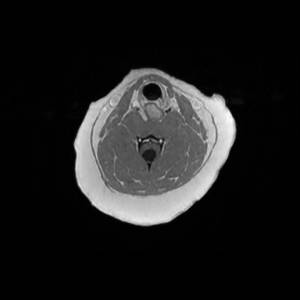

Main Gallery

Playing with a photo gallery function. It is possible to have multiple galleries, each within a namespace.